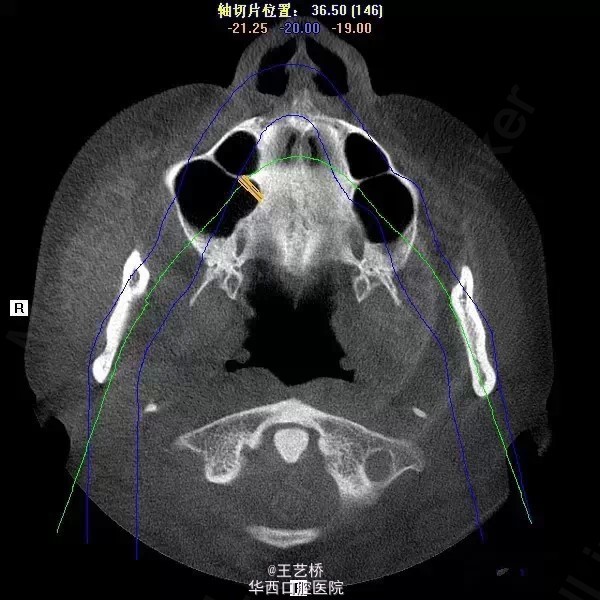

各式各样形态的上颌窦(二)

接着之前放图

上颌窦占位

上颌窦息肉